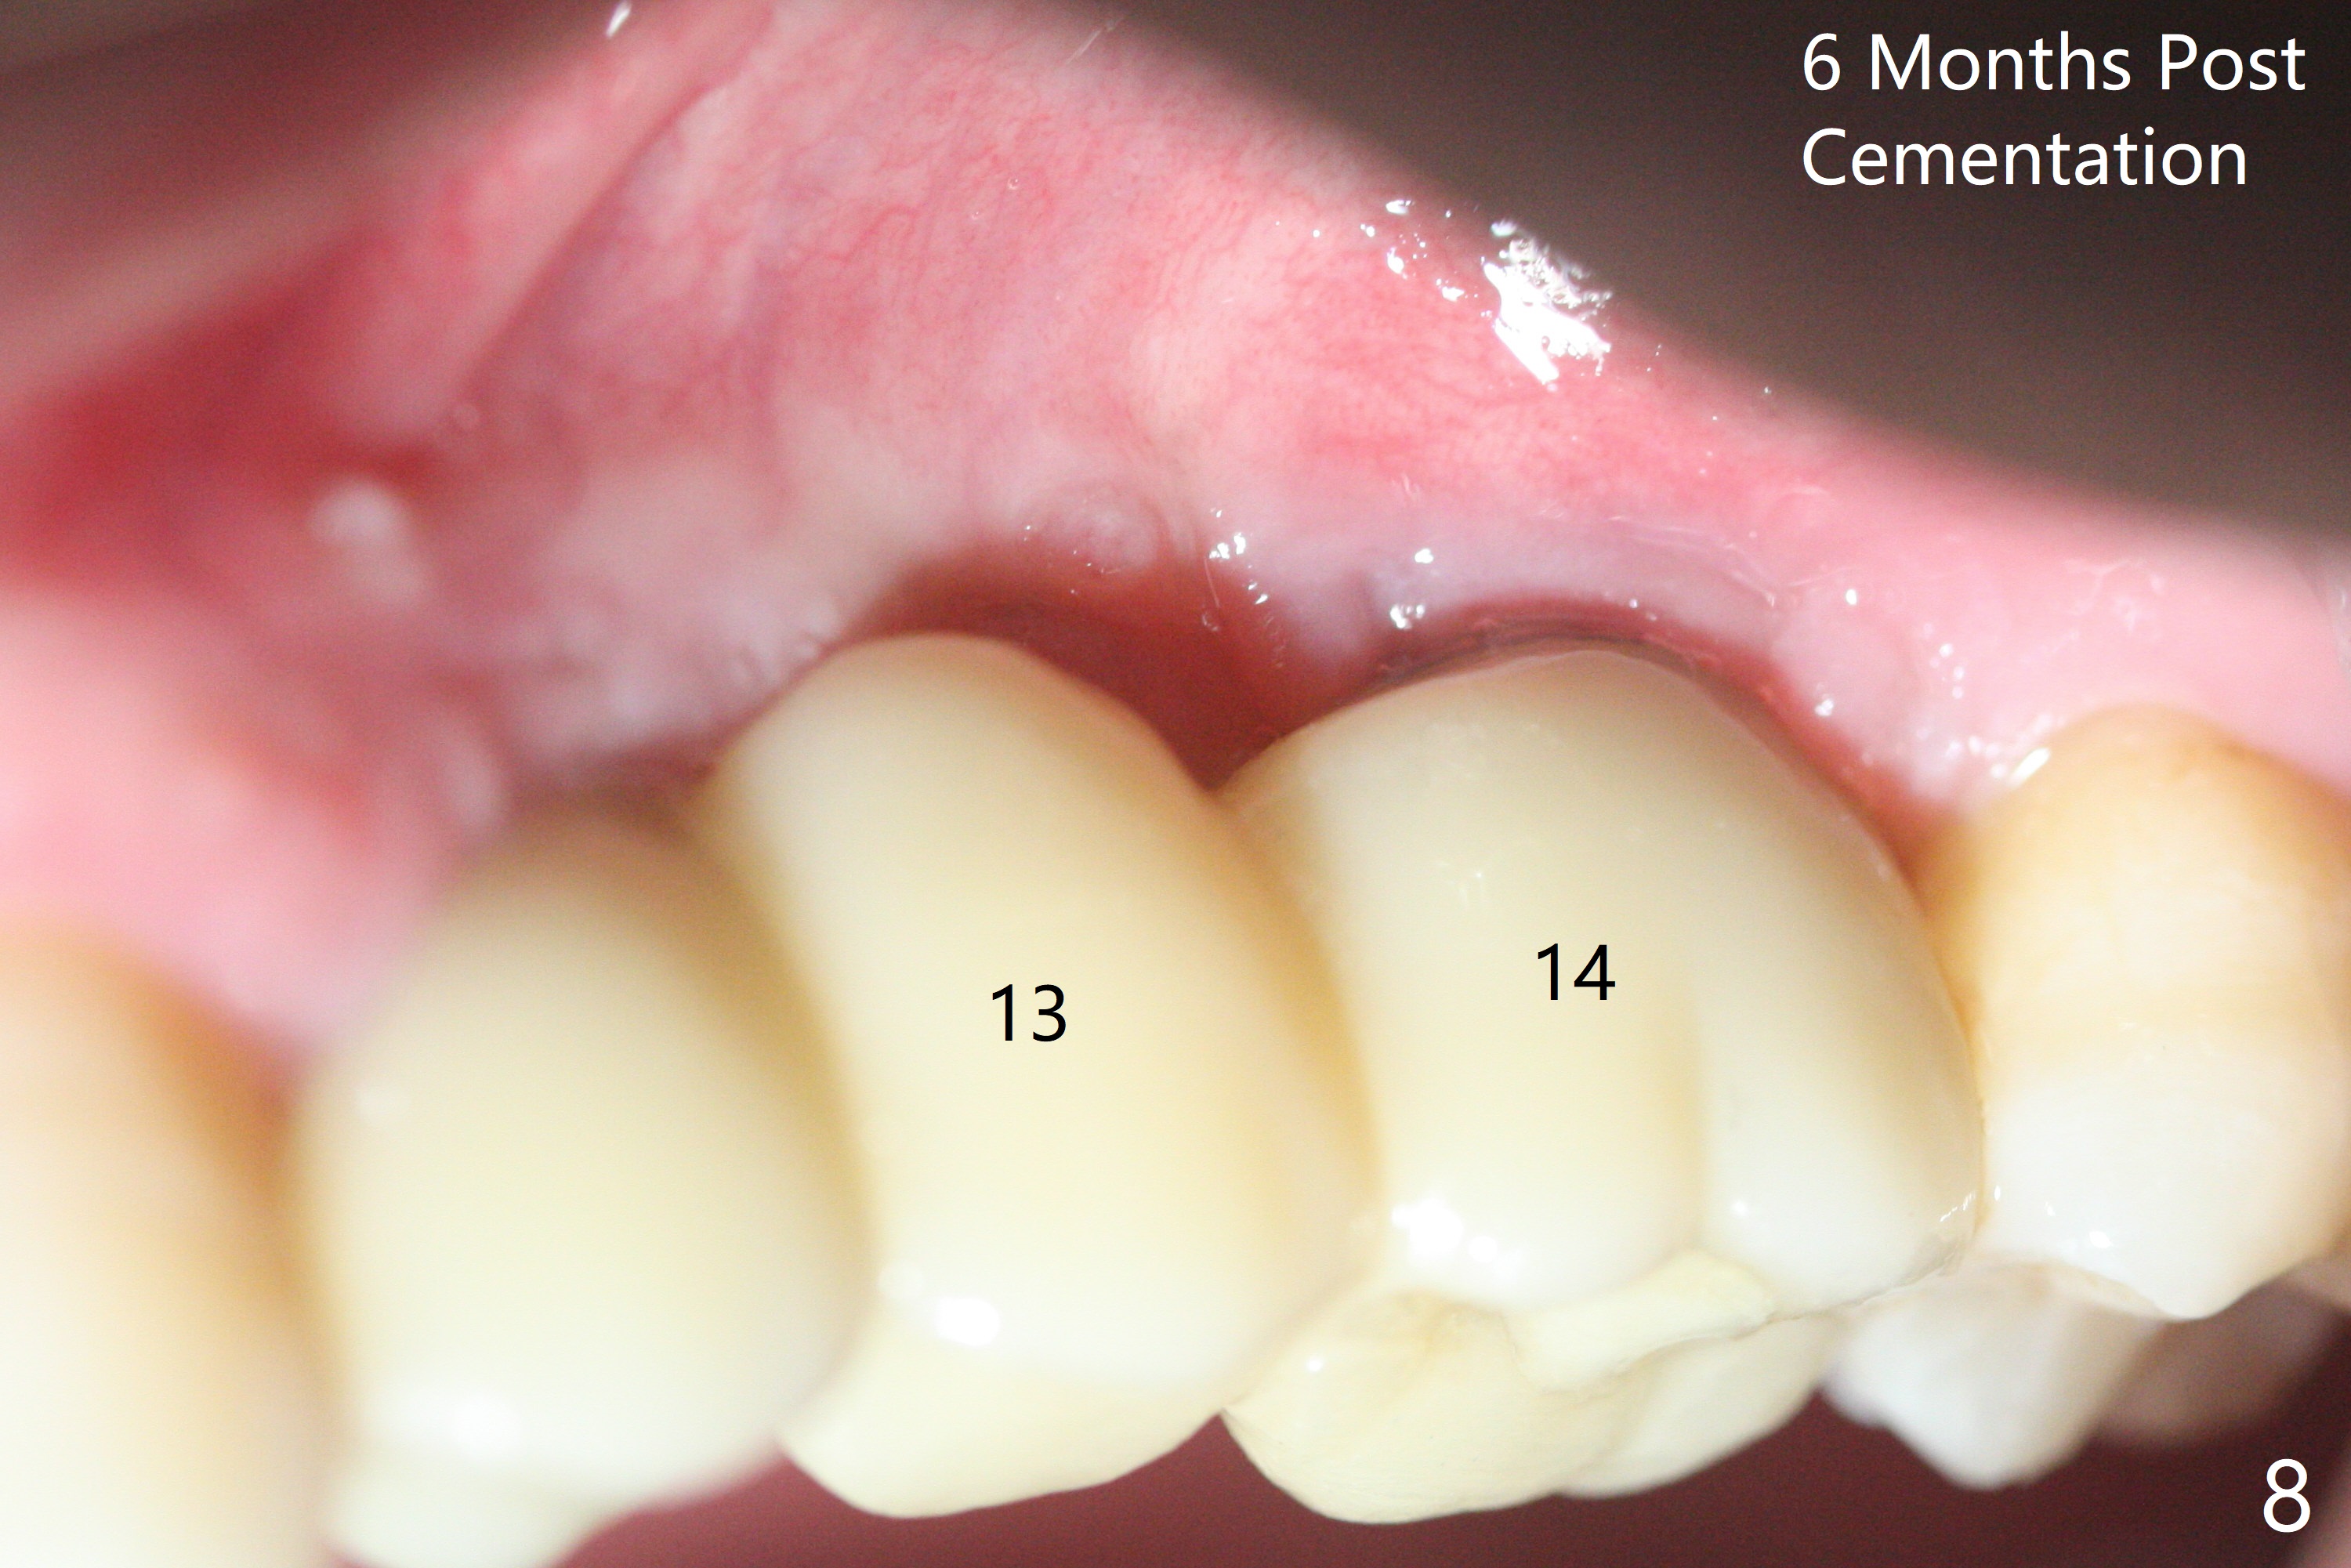

Immediate placement at #12 is smooth with 20 Ncm, whereas delayed one at #14 involves sinus membrane perforation; after insertion of PRF and mixture of autogenous bone and allograft, a shorter dummy implant tries in with stability (Fig.1). The final implant at #14 has ~60 Ncm, but the coronal palatal bone may be insuficient (Fig.2). Sticky bone is placed to bury the implant at #14 (Fig.3 *). After placement (incomplete, Fig.3 <) of a 4.5x7.5(4) mm pair abutment, setting acrylic is applied around the abutment, over the bone graft at #14 (to prevent loss) and pressed into the undercuts of the proximal surfaces of the neighboring teeth for retention (Fig.4). The sockets at #12 heals 8 days postop when a 2nd acrylic dressing dislodges (Fig.5). It appears that the retention of 3-unit acrylic dressing is poor. The wound at #14 also heals, but it would be better to make an incision to save the soft tissue (Fig.6). The bone/implant gap reduces at #13 five months postop (Fig.7 (complete abutment seating)). There is no implant thread exposure at #13 (immediate), while minor exposure mesial to #15 (delayed). The patient complains of food impaction between #13 and 14 buccally 6 months post cementation (Fig.8). Return to Upper Molar Immediate Implant, No Deviation 19 Next Case Xin Wei, DDS, PhD, MS 1st edition 01/21/2020, last revision 02/03/2021